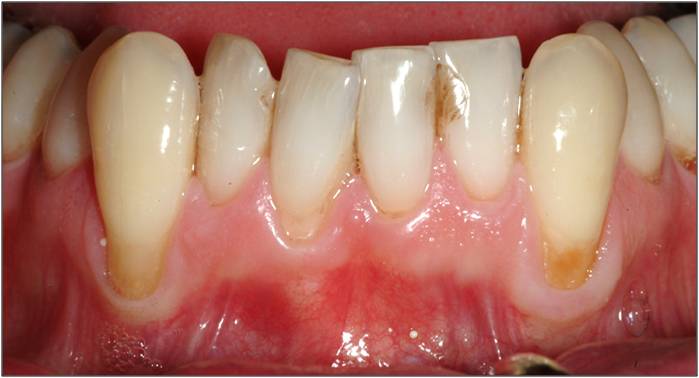

Gingivitis: This mild form of gum disease, commonly caused by poor oral hygiene, can lead to irritated, swollen, and receding gums. Maintaining good oral hygiene can prevent further periodontal problems.